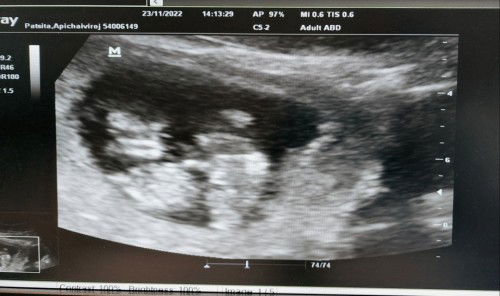

พอดีเมื่อวานเรามีนัดเจาะNiptกับคุณหมอค่ะเลยได้อัลตร้าซาวนด์ดูน้องตอน 11week6 กลายเป็นว่าจากซาวนด์ครั้งเรกเห็นแค่1คนตอนนี้น้องมี2คนค่ะ น้องขยับกันดุ๊กดิ๊กทั้งสองคนหัวใจเต้นดีขนาดตัวตามเกณฑ์ แปลกใจมากตรงที่บ้านเราเเล้วแฟนไม่มีเชื้อแฝดเลย อยากให้แม่ๆท้องแฝดธรรมชาติมาเเชร์ประสบการณ์กันหน่อยค่ะอยากรู้ว่าแฝดธรรมชาติส่วนมากคลอดกันตอนกี่วีค ต้องระวังอะไรบ้างค่ะ ส่วนมากเพื่อนๆเราเป็นแฝดทำกับคุณหมอเค้าบอกไม่ให้เดินเยอะอยากทราบว่าแฝดธรรมชาติจะแตกต่างกันไหมคะ #ขอบคุณล่วงหน้านะคะ #ท้องแฝด